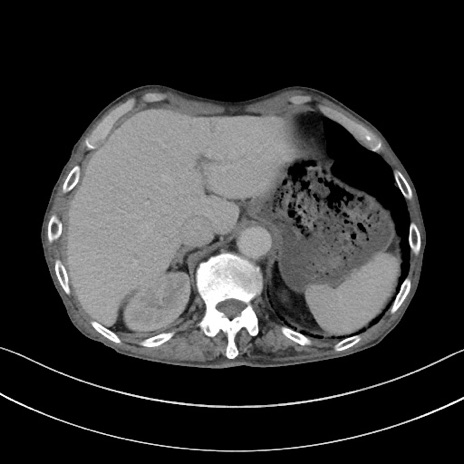

【症例】 70歳代男性

【主訴】右鼠径部腫瘤、疼痛

【現病歴】本日朝より上記主訴あり、受診。

【既往歴】膀胱癌にて膀胱全摘、両側尿管皮膚瘻

【データ】WBC 5600、CRP 0.56